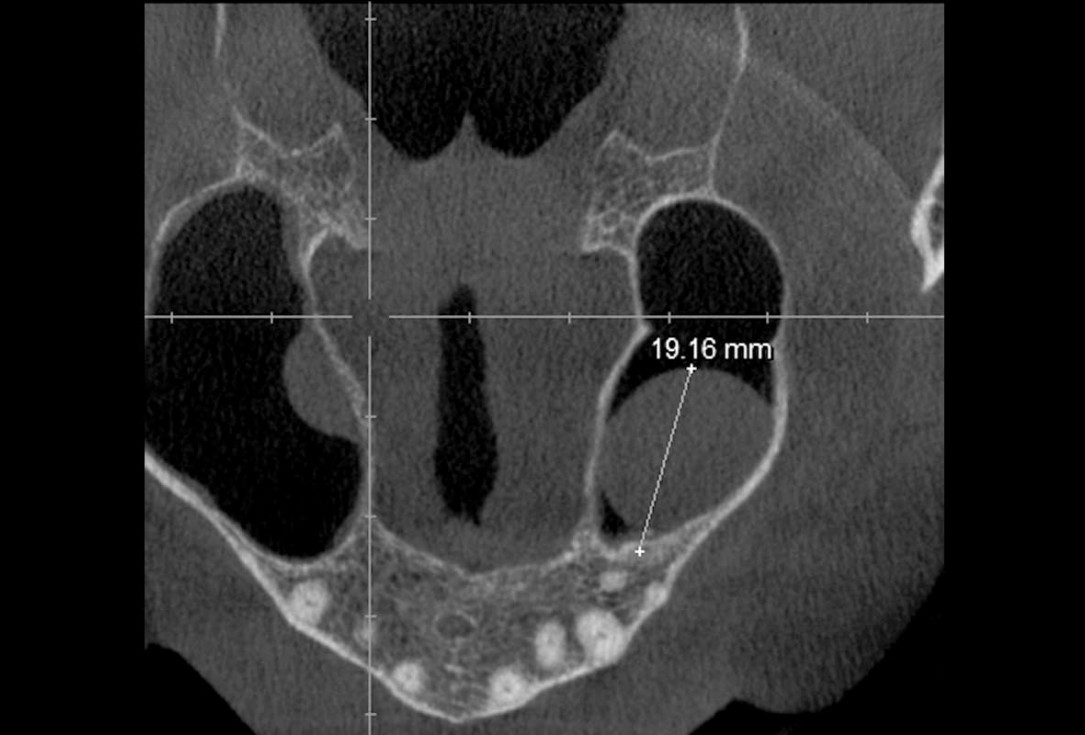

03/35 - CBCT shows maxillary sinus cystMaxillary sinus cyst removal using the Crocodile Technique and subsequent lateral sinus lift - Dres. C. Scognamiglio and A. Perucchi